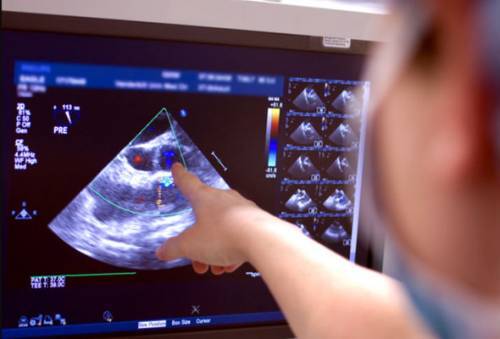

Основы эхокардиографии заключаются в отражении и улавливании ультразвуковых волн. Датчик посылает импульс, который отражается от тканей с различной плотностью. Затем аппарат улавливает сигналы, преобразуя их в графическое изображение, которое выводится на монитор.

Проходя через сердце, ультразвуковые волны поглощаются и отражаются его тканями. Благодаря этому, прибор выводит изображение на экран, по которому специалист может сделать заключение об основных параметрах работы органа.

На мониторе во время сеанса специалист может оценить такие показатели, как выраженность обратного кровотока, его скорость, размер отверстия, через которое проходит кровь.

В результате создается графическая картинка сердечной мышцы, и на мониторе врачу выводится ее двухмерное или трехмерное (в зависимости от технических характеристик прибора) изображение.

С помощью эхокардиографии врачу удается определить состояние мягких тканей и клапанного аппарата, оценить объем сердечных полостей, установить толщину стенок и сократительную способность миокарда. Кроме этого, обследование позволяет изучить деятельность сердца в режиме реального времени, а также предоставляет возможность узнать скорость кровотока в предсердиях и желудочках.